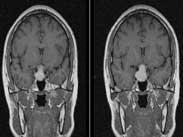

垂體卒中

• 垂體卒中

628健康網(wǎng)為您分享有關(guān)垂體卒中的癥狀,垂體卒中的治療方法,垂體卒中的預(yù)防知識(shí),垂體卒中的癥狀圖片,垂體卒中吃什么藥,垂...